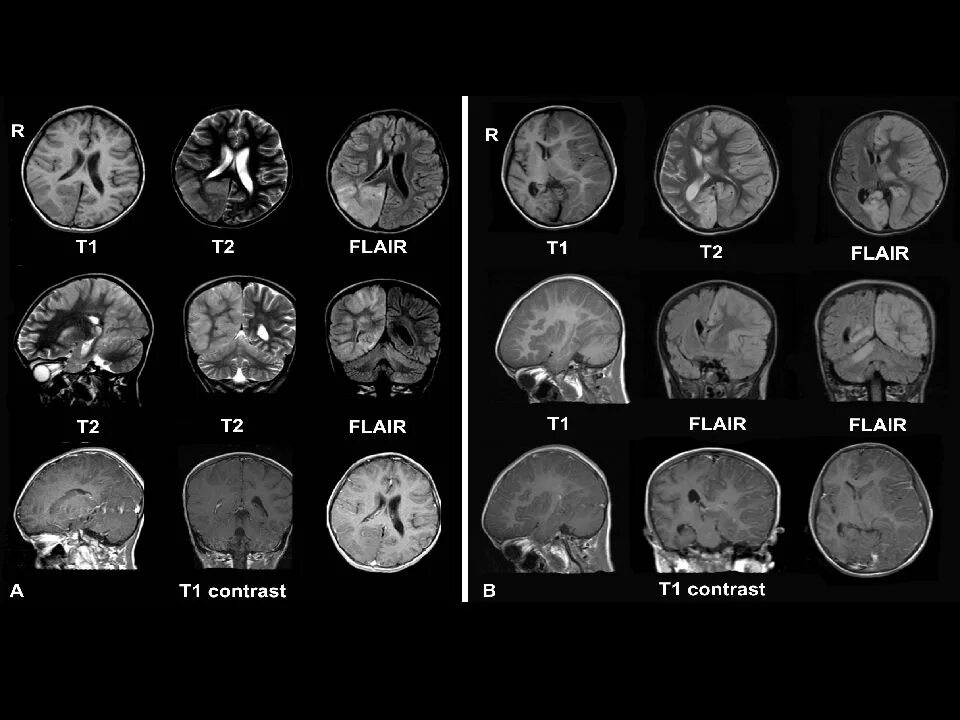

Повторный энцефалит